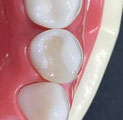

精密な光学カメラでお口の中を撮影するので、従来の粘土のような型取り材の変形がなく、

高精度な詰め物、被せものを作製することができます

詰め物と被せものの間に隙間がないため、2次虫歯を防ぐことができます

規格化された高品質なセラミックブロックを使用するため、天然の歯に近い透明感を見た目の美しさが実現でき、長期間きれいさが続きます